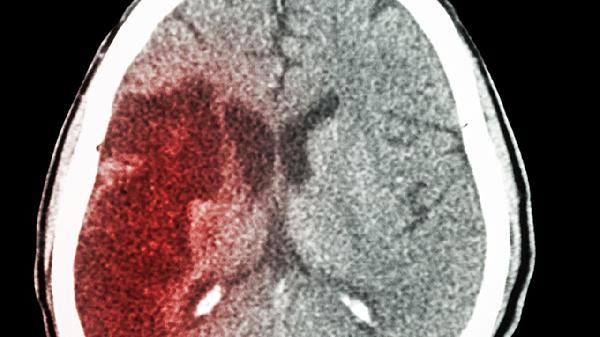

脑梗来袭,睡觉先知!如果睡觉时出现四种异常表现,小心脑梗发生

深夜翻身时突然手臂发麻?晨起发现枕头湿了一片?这些容易被忽略的睡眠细节,可能是大脑发出的求.救信号。脑血管专家提醒:睡眠是观察脑部健康的黄金窗口。